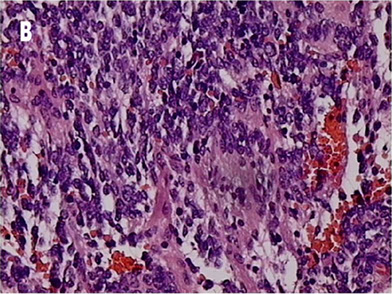

Ganglioneuroblastoma

mix of immature neuroblasts and ganglion cells, stroma has lots of Swann cells

Micro: Neuroblasts can have Homer Wright pseudorosettes, minimal cytoplasm, salt n peppa chromatin

- Ganglion cells have lots of red cytoplasm, more well defined, big nuclei

- small round blue cell (neuroblastemal) component is neuroblastoma